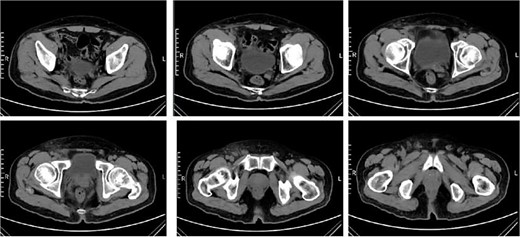

A follow-up complete blood count was normal and C-reactive protein 21.8 mg/L, PCT 0.09 ng/ml. CT re-examination indicated that the right inguinal lymph nodes had decreased in size (Fig. 6). Subsequently, the prednisone dosage was reduced by 5 mg every 7 days until discontinuation, with no further fever symptoms reported.